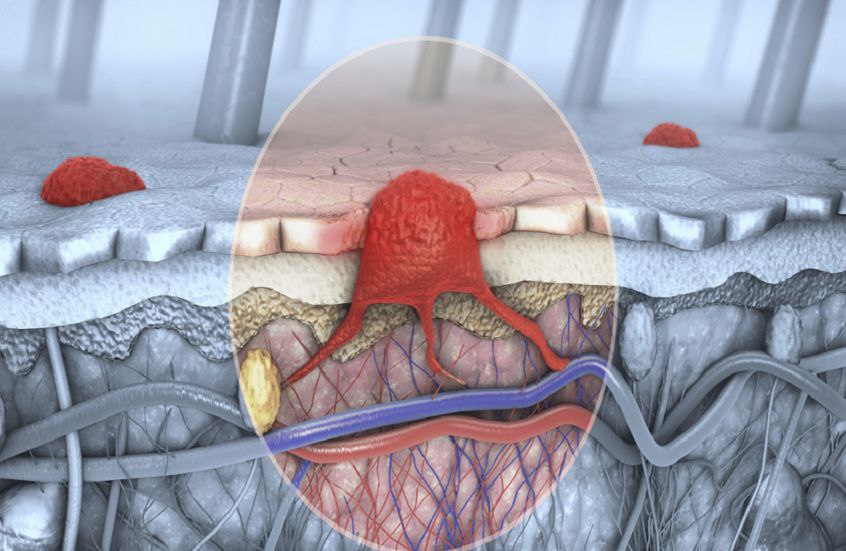

وقال ويلز: “يعد هذا العلاج الأول من نوعه، ليس فقط للوقاية من سرطان الجلد، بل أيضا لعلاج الحالات المبكرة لدى مرضى زراعة الأعضاء، الذين يتعرضون بشكل أكبر للإصابة بأنواع معينة من سرطان الجلد، مثل سرطان الخلايا الحرشفية وساركوما كابوزي، نتيجة تناولهم الأدوية المثبطة للمناعة للوقاية من رفض الأعضاء”.

وأوضح أن “المرضى الذين خضعوا لزراعة الأعضاء يواجهون تحديات كبيرة في علاج سرطان الجلد، حيث لا توجد أدوية معتمدة من إدارة الغذاء والدواء الأمريكية (FDA) تستهدف بشكل خاص سرطان الخلايا الحرشفية لدى هذه الفئة”، معتبرا “أن العلاج الجديد قد يكون “تحويليا” بالنسبة لهؤلاء المرضى، حيث يوفر خيارا مبتكرا وآمنا يعزز نوعية حياتهم”.